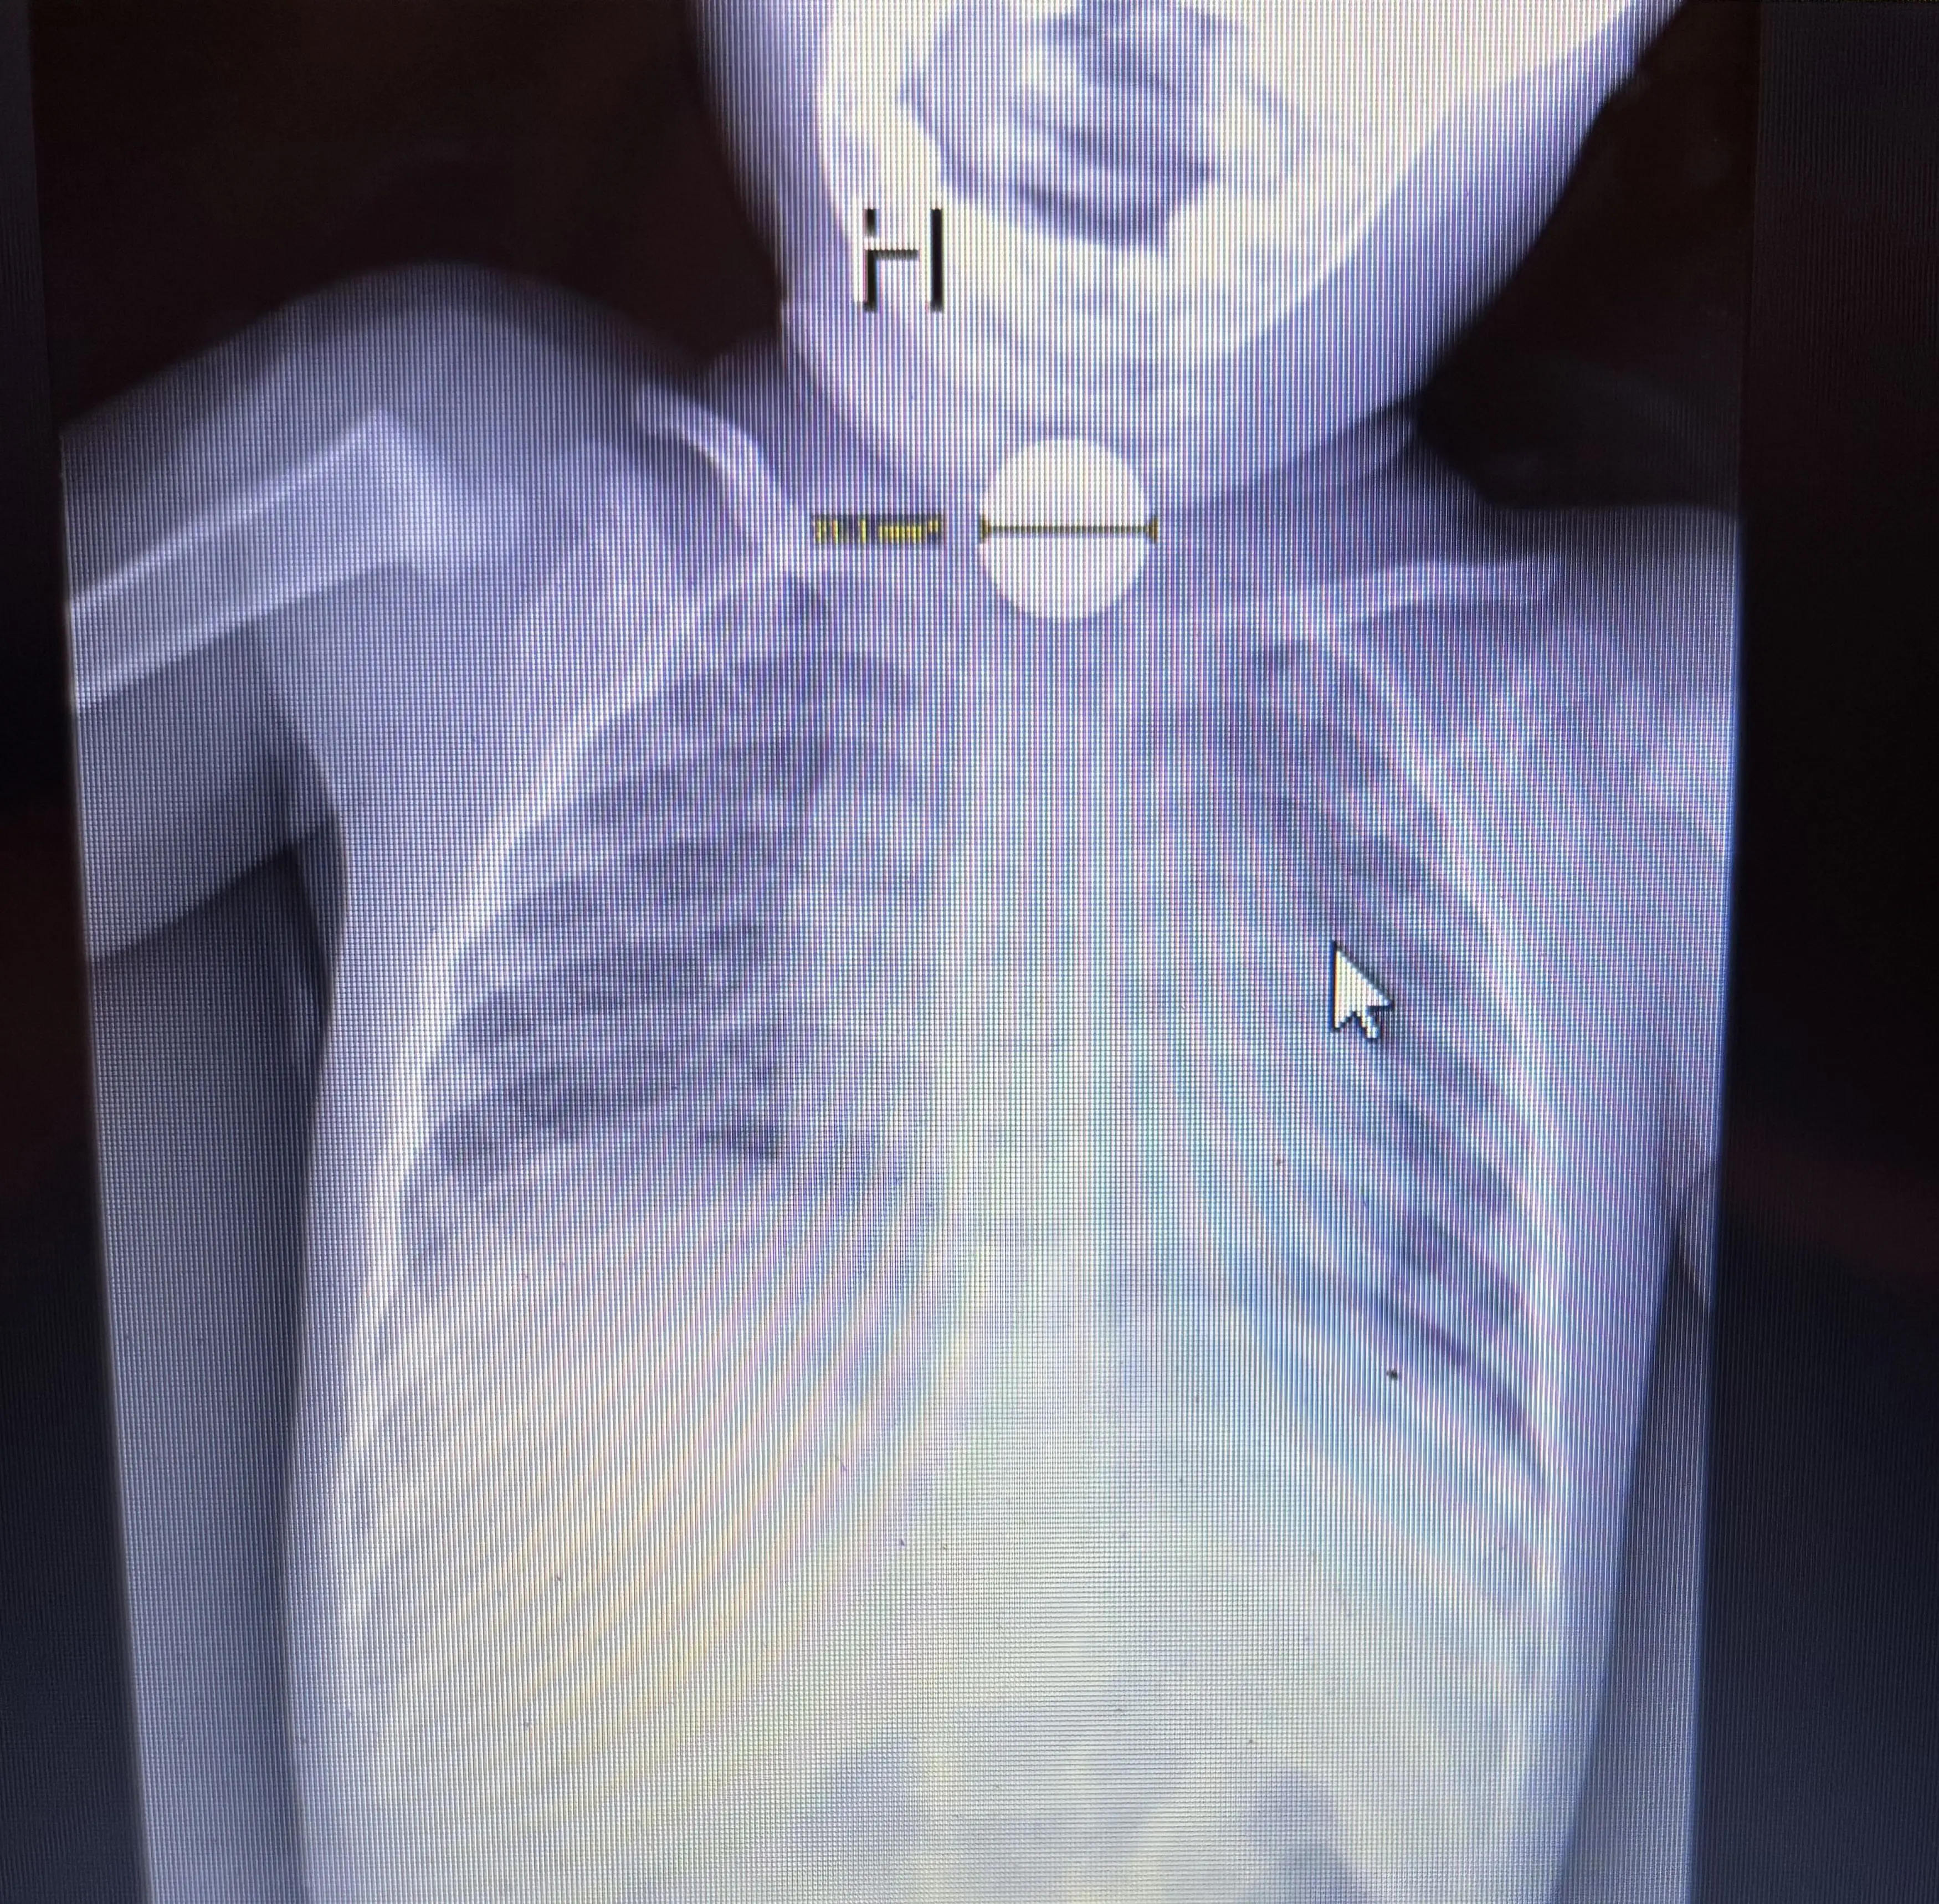

However, Madeline believed that it was something far worse and after pushing for an X-ray scan, it was revealed that Kai had swallowed a button battery which was burning its way through his throat.

"When we were walking back to the room there was already a team of doctors waiting in the room with him and they had the x-ray pulled up which showed the button battery in his throat.

"They were saying he'd swallowed a button [battery] - it's code red. They started shoving honey down his throat and getting him prepared to rush him into surgery.”

Shockingly, Kai’s oesophagus was left blackened thanks to the battery and a CT showed that it had been left with a hole in it.